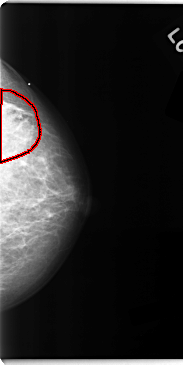

C_0113_1.LEFT_CC

LEFT_CC LINES 4736 PIXELS_PER_LINE 2368 BITS_PER_PIXEL 12 RESOLUTION 50 OVERLAY

FILE: C_0113_1.LEFT_CC.OVERLAY

TOTAL_ABNORMALITIES 1

ABNORMALITY 1

LESION_TYPE MASS SHAPE IRREGULAR MARGINS ILL_DEFINED

ASSESSMENT 5

SUBTLETY 3

PATHOLOGY MALIGNANT

TOTAL_OUTLINES 1

BOUNDARY